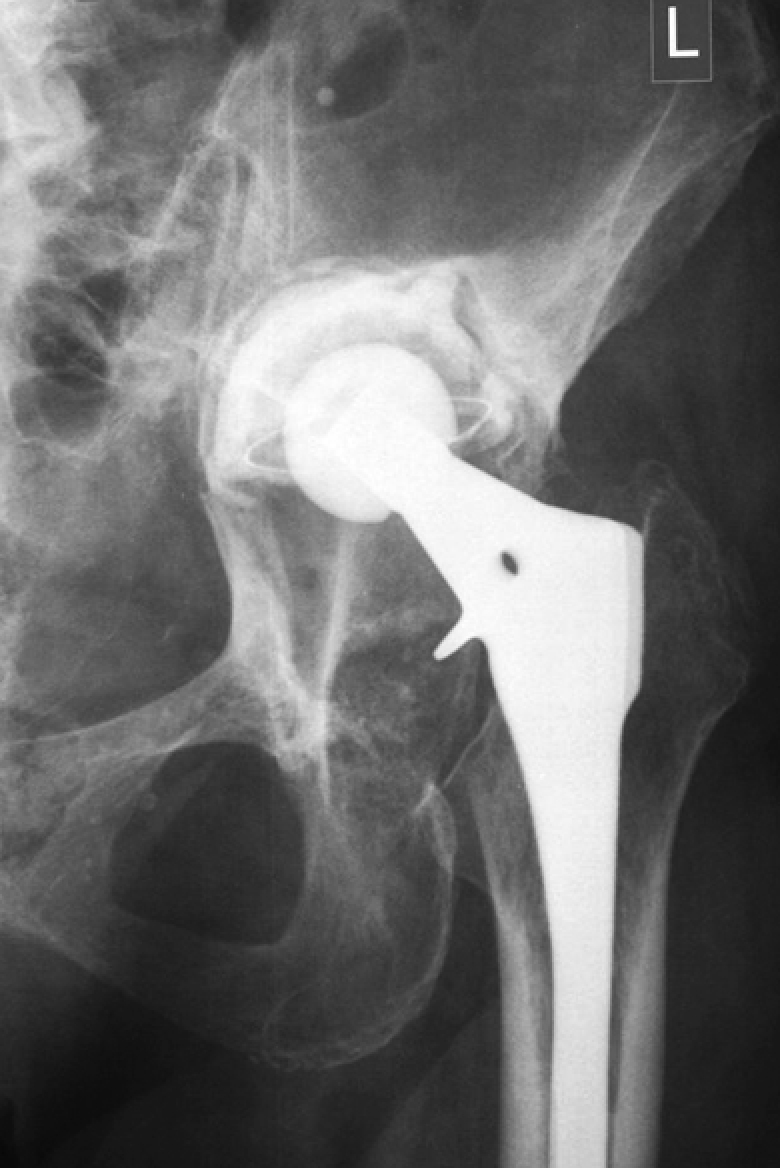

X-rays of patients with defects | ||||

Three-dimensional reconstructions of the pelvis of the same patients from the side of defect | ||||

Lytic defects and complete defects of the anterior column, despite their extent, require the restoration of the sphericity of the acetabular region, which can be reconstructed using bone grafts, augments, and standard hemispherical components (Figure 2 a, b).

Figure 2. Various options for acetabular reconstruction in Paprosky type 3B defect: a — lytic acetabular defect reconstructed using impaction bone grafting with implantation of a standard cemented acetabular component; b — complete anterior column defect reconstructed with an augment and a hemispherical acetabular component; c — complete medial wall defect reconstructed with augmentation and combined implantation of a hemicap cage; d — combination of complete medial wall and anterior column defects reconstructed with a Burch-Schneider antiprotrusio cage and a cemented acetabular component; e — combination of complete medial wall and posterior column defects reconstructed with a patient-specific acetabular component